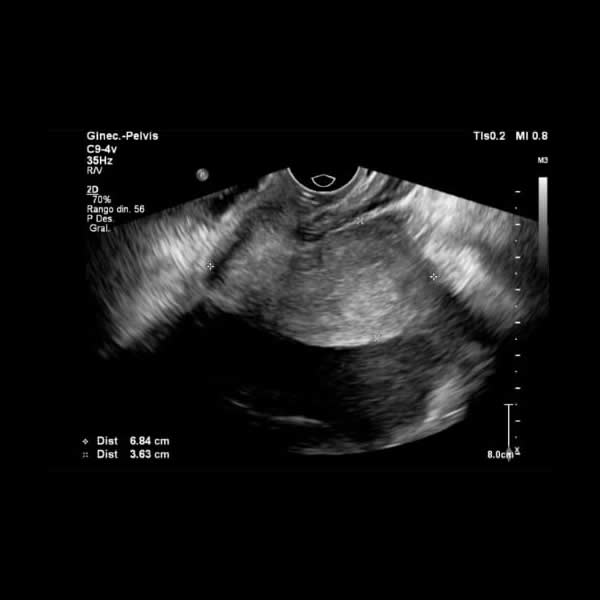

Mayo 2023. Sanatorio Del Salvador Paciente femenina de 20 años, sin APP, consulta por dolor abdominal agudo.